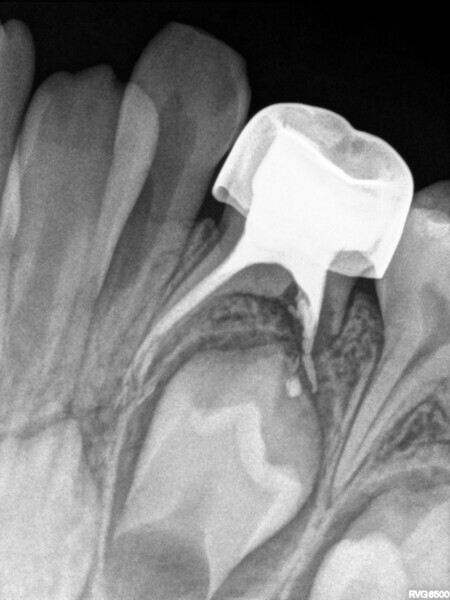

Cas 4 (Figs. 14 à 18)

Ce patient âgé de 4 ans et 6 mois présentait une douleur constante qui était apparue spontanément au niveau de la première molaire temporaire inférieure gauche, et persistait depuis plusieurs jours. Toutefois, aucun œdème facial ou gonflement du versant vestibulaire de la gencive n’était visible. Des caries profondes étaient présentes, mais il n’y avait ni mobilité dentaire ni profondeur de poche importante au sondage. La radiographie montrait un risque d’effraction de la cavité pulpaire lié à la lésion carieuse, et une atteinte de la zone de furcation correspondant à un défaut osseux. Une pulpectomie était le traitement de choix. L’élimination de la lésion carieuse a entraîné une exposition de la pulpe, mais aucun saignement n’a été observé. Une nécrose pulpaire a été diagnostiquée. Quatre canaux, deux mésiaux et deux distaux, ont été localisés et la dent a été obturée. Lors du second rendez-vous, la dent était asymptomatique et elle a été restaurée au moyen d’une couronne en acier inoxydable. À la visite de suivi à 30 mois, la dent ne présentait aucun symptôme et la radiographie a montré un processus éruptif normal.